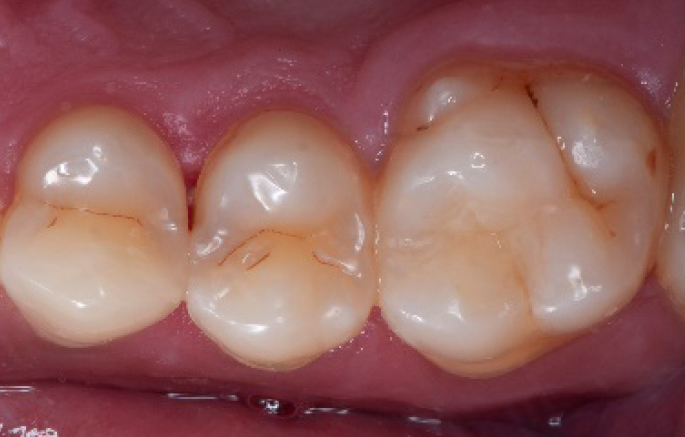

After

Final situation 2 weeks after the filling. Great comfort and no sensitivity at all were reported by the patient.

Step 13:

Occlusal check

Step 14:

2 weeks control